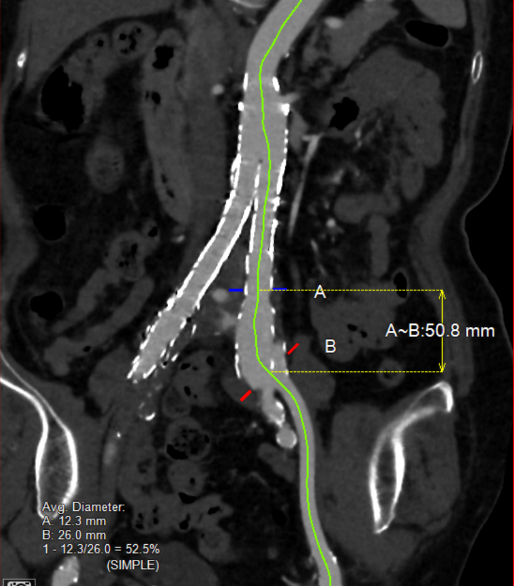

术前测量评估:

gore医疗怎么样「漫腹精论」独具匠心 推陈出新——同侧IBE支架内翻山重建髂内动脉治疗EVAR术后内漏病例报道_https://www.jmylbn.com_新闻资讯_第8张

gore医疗怎么样「漫腹精论」独具匠心 推陈出新——同侧IBE支架内翻山重建髂内动脉治疗EVAR术后内漏病例报道_https://www.jmylbn.com_新闻资讯_第9张

术前主动脉CTA提示:左侧髂总动脉瘤样扩张,支架外见造影剂显影,瘤体内IMA开口水平亦可见造影剂显影,考虑左髂Ib型内漏合并IMA来源II型内漏可能。

患者全麻满意后,穿刺左股动脉,置5F导管鞘。左侧泥鳅导丝配合标记猪尾导管至腹主动脉上段造影:双侧肾动脉显影,腹主动脉内支架在位通畅,近端未见明显内漏,右侧髂总动脉支架在位,未见明显造影剂外渗,右侧髂内动脉未见显影;左侧髂总动脉支架远端瘤样扩张,大小约3.0cm*2.5cm,可见支架外造影剂外渗,考虑Ib型内漏可能,左侧髂内动脉开口处稍狭窄。